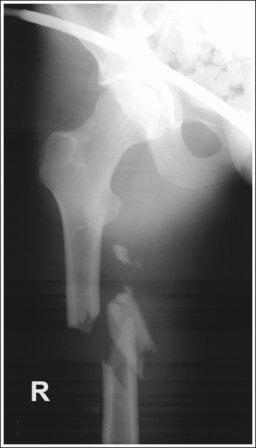

See Figures 6-103 and 6-104 and Boxes 6-21 and 6-22.

Image density is uniform across the femur.

• Position the thicker proximal femur at the cathode end of the tube and the thinner distal femur at the anode end to take advantage of the anode heel effect and obtain more uniform density across the femur.

• Positioning for femoral fracture. When a patient has a fractured femur, the leg should not be internally rotated, but left as is. Forced internal rotation of a fractured femur may injure the blood vessels and nerves that surround the injured area. Because the leg is not internally rotated when a fracture is in question, the distal femur demonstrates external rotation.